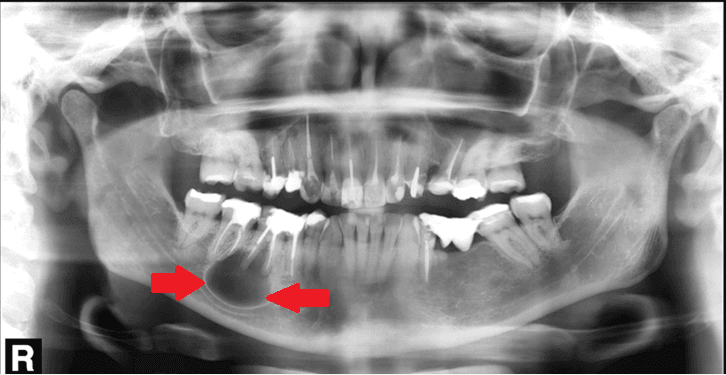

A radiografia panorâmica é indispensável para a avaliação de possíveis lesões endodônticas, inclusive em dentes que já tenham tratamento de canal realizados. Visto que a movimentação ortodôntica pode agudizar processos infecciosos que estejam “adormecidos”.

A presença de núcleo metálico fundido, é um fator que aumenta a probabilidade de fratura de um elemento dentário, principalmente elementos que possuem pinos que apresentam mais de 1/3 da largura da raiz do dente. Com isso é de extrema importância que o responsável observe a radiografia panorâmica do paciente para analisar as necessidades clínicas, e notificar o paciente se há necessidade de um retratamento ou troca de pinos e coroas. O indicado é que seja feito previamente a instalação dos alinhadores, pois qualquer fratura ou perda de coroa durante o tratamento é prejudicial e podem gerar em custos extras como extensão de cobertura por exemplo.

A reabsorção é uma perda progressiva da estrutura da raiz ou da coroa do dente, vários são os fatores etiológicos, tempo de tratamento, tipo de movimentação, força aplicada, traumatismos e predisposição individual. Dentes que já possuem reabsorções devem ser monitorados, pacientes com reabsorção radicular podem usar alinhador desde que estejam dentro dos padrões de segurança de ter a mesmo tamanho de dente fora do osso e dentro do osso. Casos com reabsorções avançadas, apenas devem ser tratados por profissionais experientes que tenham avisado ao paciente dos riscos e que façam acompanhamento radiográfico constante (além do solicitado pela ezaligner).